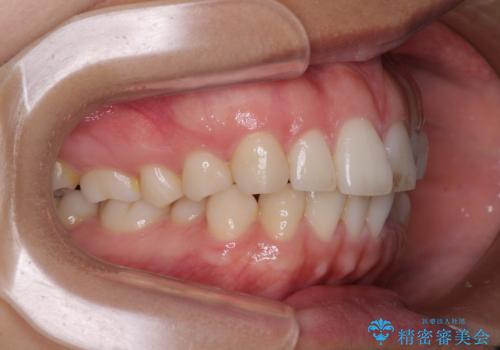

【モニター】突出した前歯 補助装置を併用したインビザライン矯正

- 上下前歯が非接触となり、前方に突出していることを気にして来院された患者様です。

咬合力が強く、全体的に歯がすり減っているため、インビザライン単独での上顎歯列移動は困難と判断し、補助装置により上顎歯列を後方移動させ、その後インビザラインにて仕上げていくこととしました。

補助装置なしでも改善できる可能性はありましたが、補助装置で確実性を上げ、短期間できっちりと仕上げることができました。